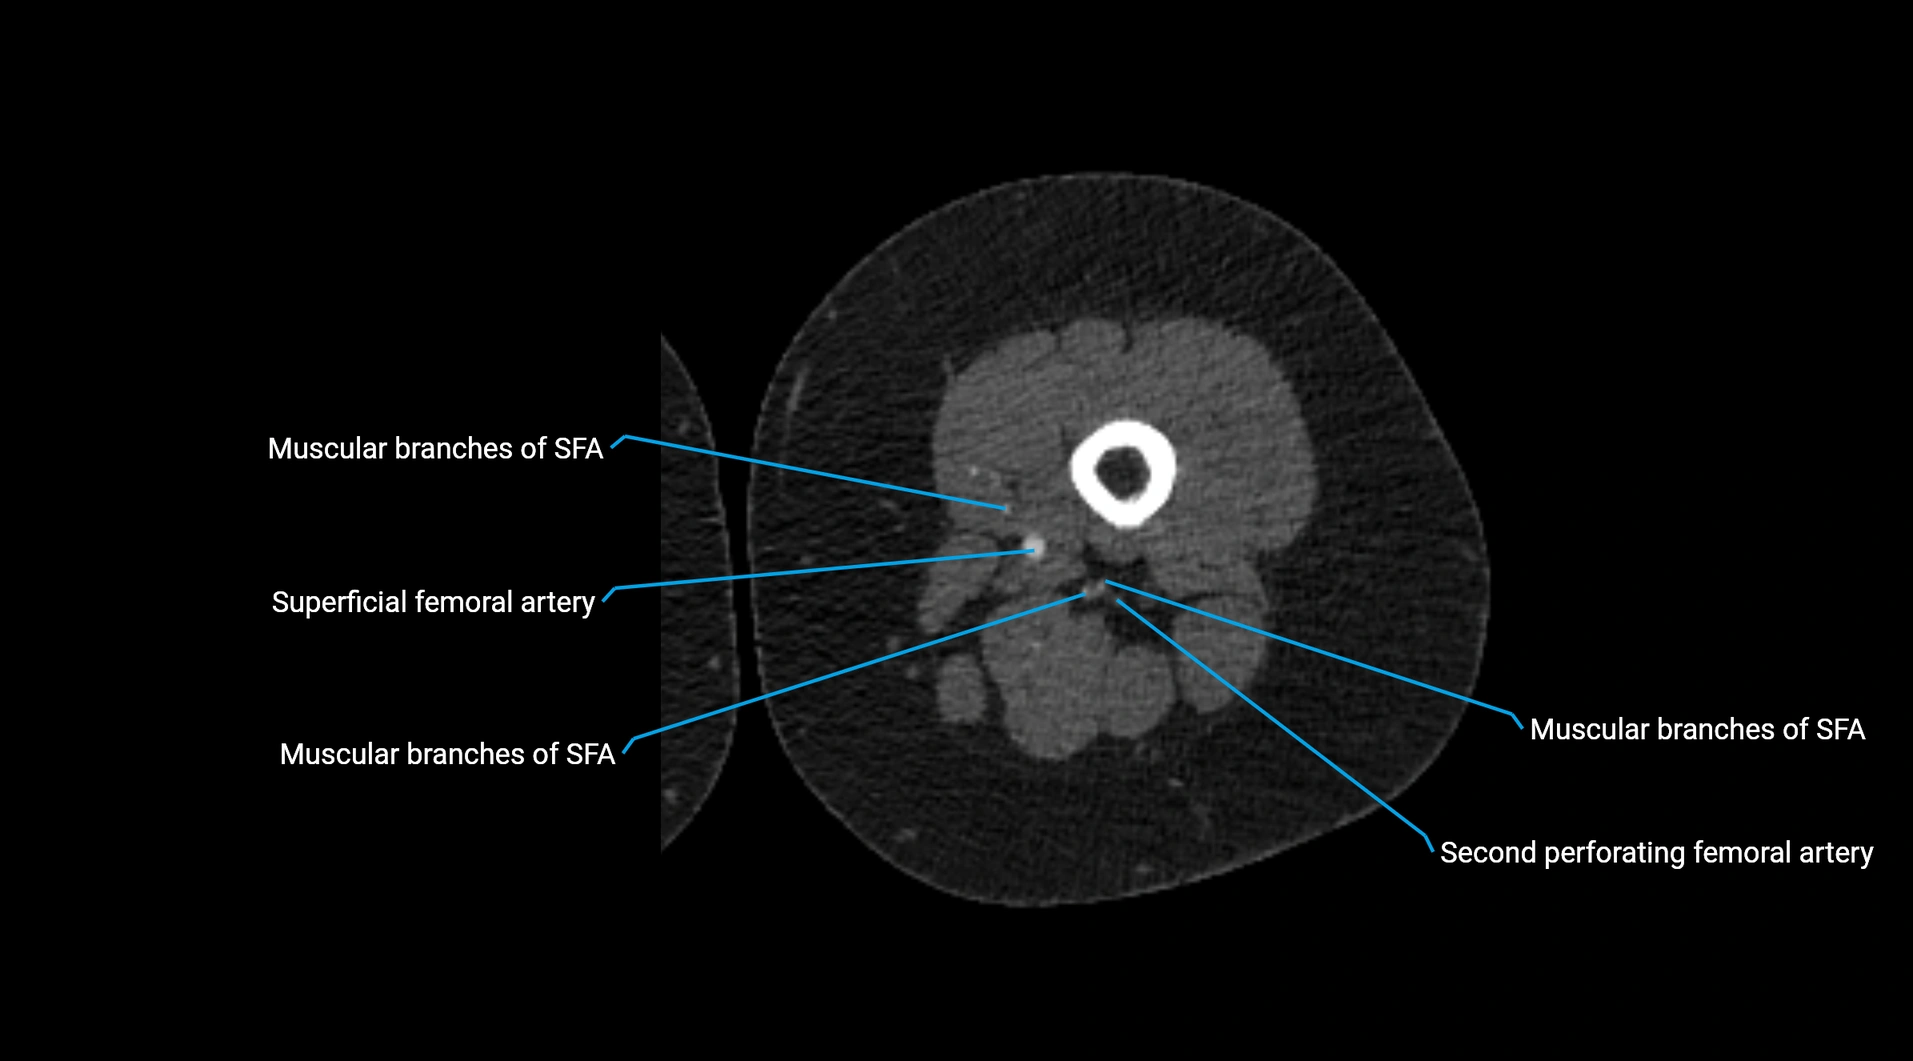

Contrast-enhanced CT (CTA):

• Gold standard for abdominal aortic imaging

• Provides excellent detail of lumen, wall, aneurysm, thrombus, and branch vessels

• Multiplanar and 3D reconstructions help in aneurysm measurement, stent graft planning, and dissection evaluation

• Detects acute rupture, traumatic injury, or occlusion with high sensitivity